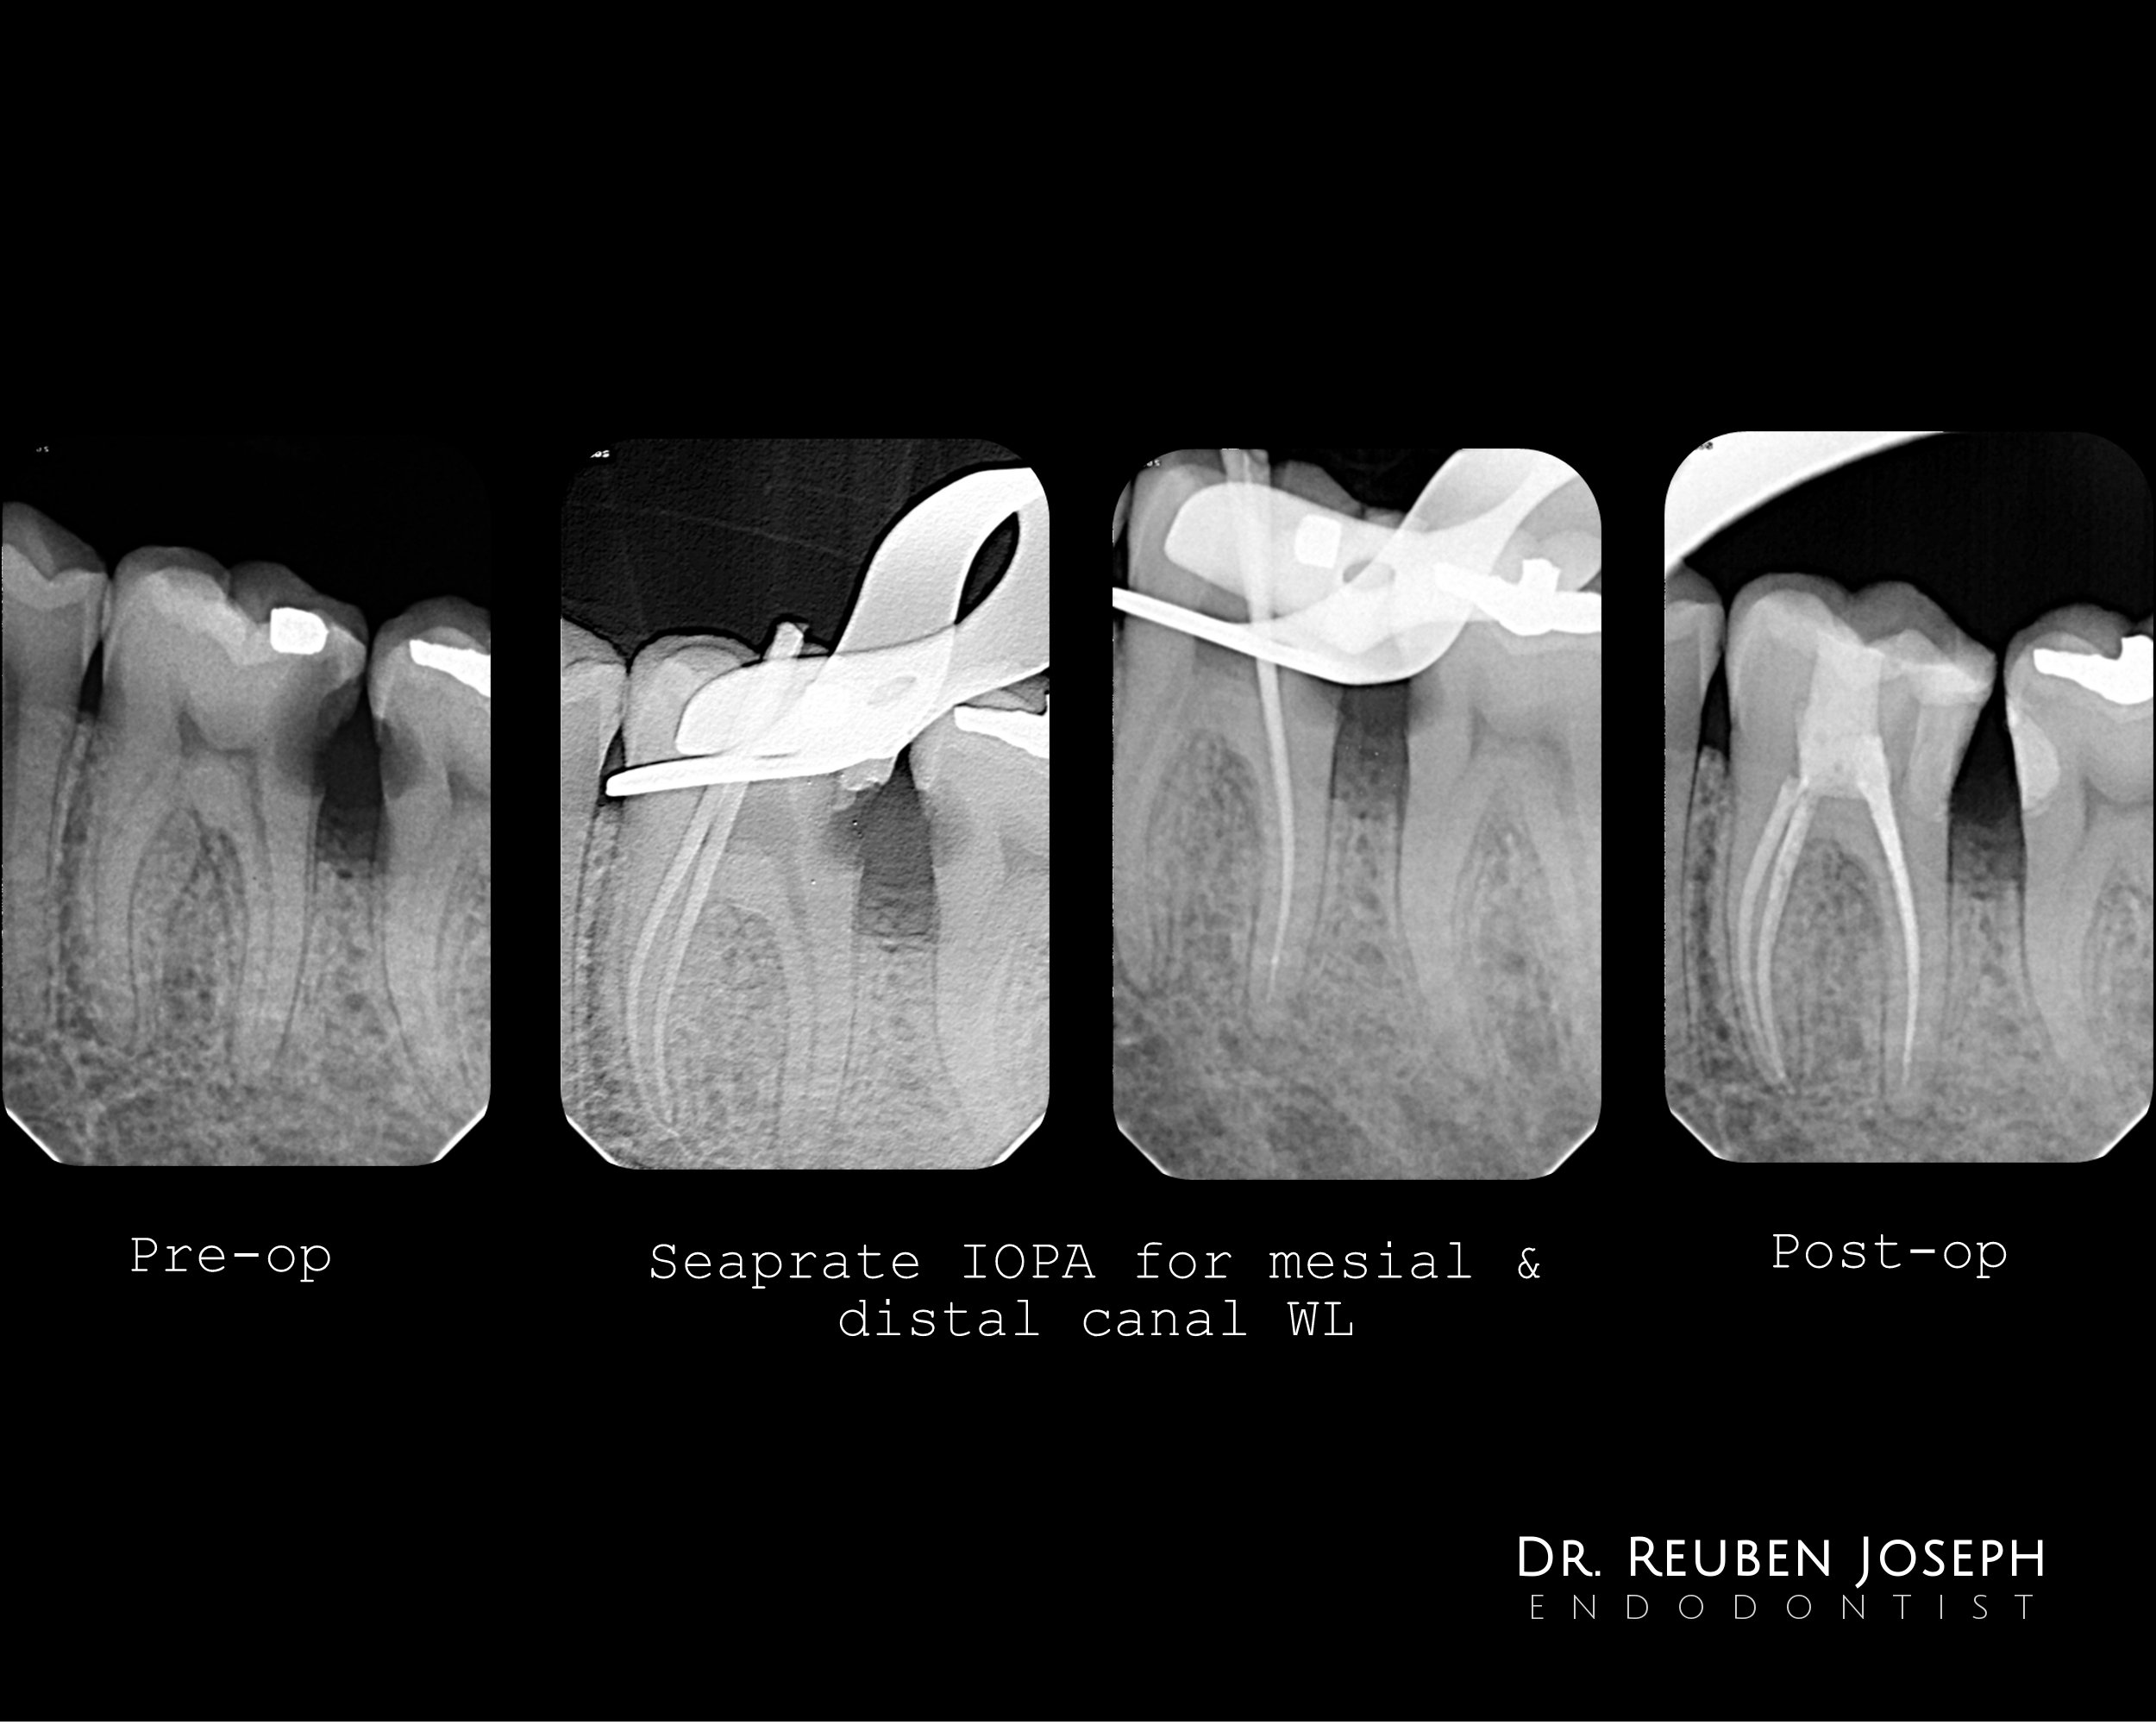

– In this case i opted for an access to the centre (place where the orifice projects) and restored the distal half separately

– The usual shaping and cleaning protocol and also restored the mesial slot in the 47 through the space i got with a open distal margin in 46. 47 is symptomatic as well and to be attended to soon.

Dr. Reuben Joseph’s profile is impressive—he’s clearly carved out a reputation for precision and innovation in openskycc endodontics. Winning the IACDE Award for Clinical Excellence in 2017 highlights his skill, but what really stands out is his focus on microscope-assisted, minimally invasive root canal treatments.